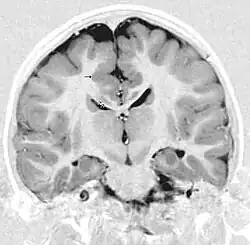

Gray matter heterotopia

Gray matter heterotopia is a neurological disorder caused by gray matter being located in an atypical location in the brain.[1]

Gray matter heterotopia are common malformations of cortical development known as neuronal migration disorders. Heterotopias are classed in two groups: nodular and diffuse. Nodular types are subependymal and subcortical; diffuse types are termed band heterotopias. Affected patients are generally divided into three groups, depending on the location of the formation: subependymal, subcortical, and band heterotopia. In addition, especially with heterotopia that are genetically linked, there are sex differences. Men seem to develop more severe symptoms than women with similar formations.

Periventricular means beside the ventricle, while subependymal (also spelled subepydymal) means beneath the ependyma; because the ependyma is the thin epithelial sheet lining the ventricles of the brain, these two terms are used to define heterotopia occurring directly next to a ventricle. This is by far the most common location for heterotopia. Patients with isolated subependymal heterotopia usually present with a seizure disorder in the second decade of life.

Subependymal heterotopia present in a wide array of variations. They can be a small single node or a large number of nodes, can exist on either or both sides of the brain at any point along the higher ventricle margins, can be small or large, single or multiple, and can form a small node or a large wavy or curved mass.